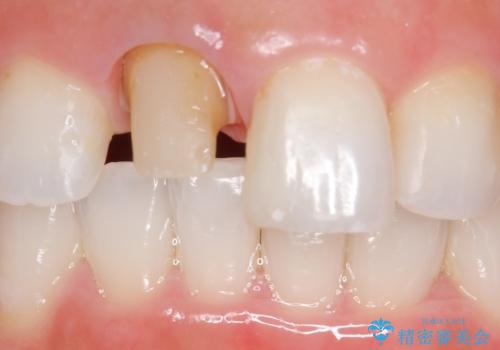

- 右上1の前歯の見た目が気になるので被せ物をやり替えたいといらっしゃった方の症例です。

再根管治療終了後、オールセラミッククラウン(スペシャル)によって隣在歯に合わせた補綴を行いました。